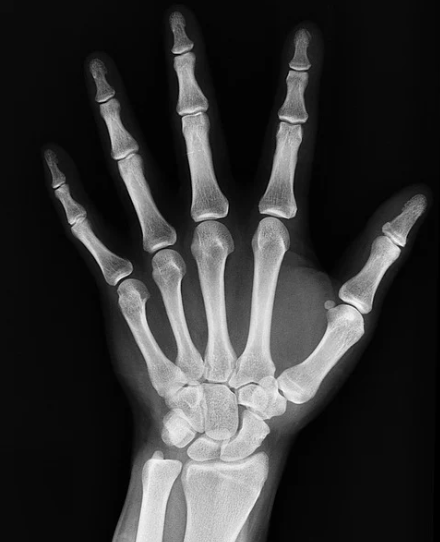

뼈에 금이 갔을때 먹으면 좋은 음식

뼈에 금이 가게되면 뼈가 잘 달라붙을때까지 몇주에서 몇달까지도 깁스를 하게되는 경우가 있습니다. 사람마다 뼈다 달라 붙는 기간이 다른 만큼 뼈에 좋은 음식을 먹으면 뼈가 잘 붙을 수있도록 도움을 줄 수도있을 것같은데요. 그럼 뼈에 금이 갔을때 좋은 음식에 대해 알아보겠습니다.

뼈에 금이 갔을때 좋은 음식은 누구나 다 아는 칼슘이 풍부한 섭취하는 것입니다. 칼슘이 풍부한 음식중 대표적인 멸치라던지 우유냐 치즈, 야채나 과일, 마그네슘이 풍부해 칼슘의 흡수를 도와주는 호두등이 있습니다. 뼈에 금이 갔을때에는 술이나 설탕등을 멀리해 주시면 좋습니다.